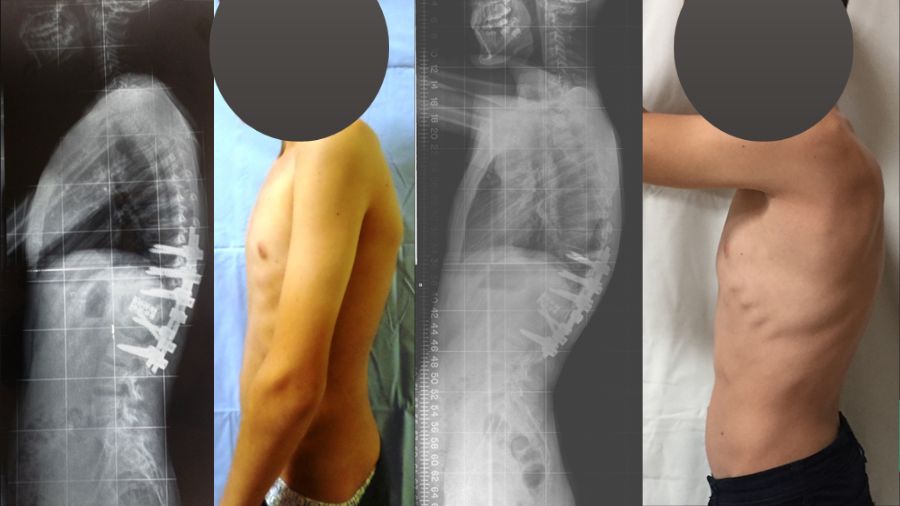

Nevertheless, these are high-risk and invasive surgeries, and the best treatment option is always early intervention. If the disease has only local impacts and no neural deficit and deformity, the patient can undergo anti-TB chemotherapy and wear a brace for a year, or a year and a half. Sometimes, this prevents the progression of the disease and surgery is not required. Sadly, for too many patients, diagnosis only happens when the spinal deformity is already very severe. This makes it crucial that medics are able to spot the signs of TB and get our patients the help they need.

Complex spine case: post-spinal tuberculosis deformity

Alpaslan Şenköylü presents a complex case of post-tuberculosis spinal deformity on this AO TV 2024 must-watch interview (for registered users).